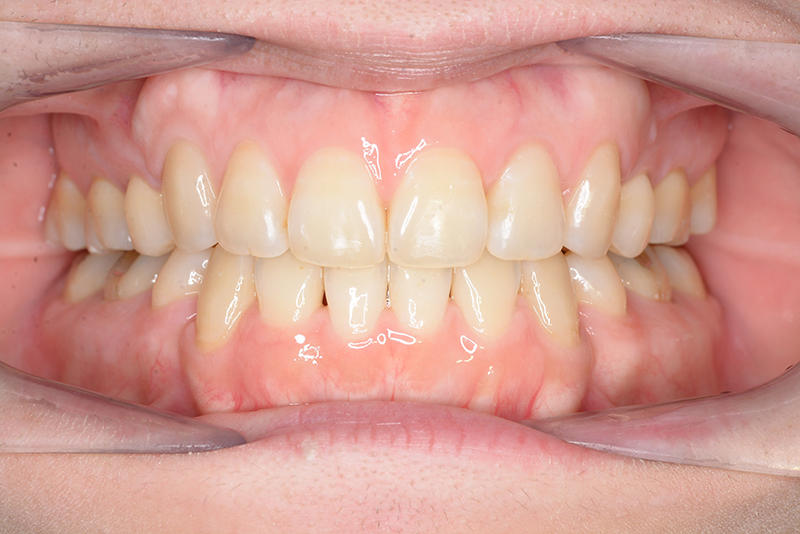

| 口腔内所見 | 臼歯関係はⅠ級、over jet 4.5mm、over bite -3.0mm。上下顎切歯部に軽度の叢生が認められ唇側傾斜をしつつ開咬を呈していた。 |

| 批評・予后 | 治療後において下顎角の開大も認められず歯軸の整直、咬合の緊密化が得られた。また上下顎前歯の後退と共に口元の突出感と口唇閉鎖不全の改善が認められた。 |